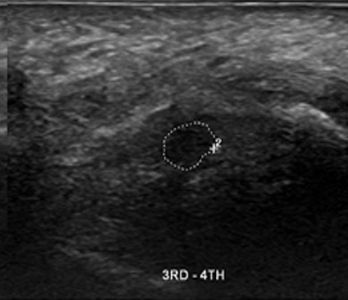

46세

남성 지간신경종

Before

2019.06.22

After

2020.02.08